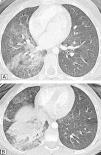

Caso clínicoNiña de 11 años que presenta emisión de sangre roja brillante por la boca, 3-4 episodios de 50ml/24h, sin antecedentes de infecciones respiratorias recurrentes ni traumatismos. Peso: 40kg (P50-75); talla: 143,5cm (P50); frecuencia cardíaca: 120 lpm; frecuencia respiratoria: 20rpm; presión arterial: 125/72 mmHg. Buen estado general. Hemodinamia, normal. Auscultación cardiopulmonar, abdomen y orofaringe, normales. Las analíticas seriadas al inicio, las 24, las 48 y las 72h posteriores fueron respectivamente: hemoglobina 13,4-12,7-11,9 y 9,3g/dl, y hematocrito de 38-37,4-34,6 y 27,3%. Las pruebas de coagulación fueron normales. La Rx de tórax al ingreso no presentó hallazgos patológicos. La fibrorrinolaringoscopia, la gastroscopia y el ecocardiograma, sin alteraciones. Evolución: en las primeras 48h persistió la hemoptisis. La angio-TC pulmonar (figs. 1–3) evidenció un tronco común con hipertrofia de arteria bronquial derecha originada en el arco aórtico adyacente en el origen de la subclavia derecha aberrante e imagen alveolar en base derecha. Se realizó una embolización endovascular selectiva (fig. 4) y una fibrobroncoscopia en el mismo acto. Se cateterizó, a través de vía femoral, la arteria bronquial de origen anómalo con hipervascularización patológica de lóbulo inferior derecho. Se utilizaron microesferas de 500-700μm en el procedimiento de embolización, con resultado satisfactorio.

En nuestra paciente, el hemograma seriado durante 48h objetivó descenso de 3g/dl de hemoglobina, sin alteraciones en las pruebas de coagulación, y la paciente permaneció hemodinámicamente estable. La angio-TC identificó la arteria bronquial derecha hipertrofiada con origen anómalo en el arco aórtico adyacente a subclavia derecha aberrante (fig. 2).

La TC ha demostrado ser de gran valor diagnóstico para determinar la causa fundamental, pudiendo localizar la fuente del sangrado en el 63-100% de los casos16. La angio-TC puede evidenciar los sistemas arteriales bronquiales y no bronquiales, y detectar lesiones vasculares17. La TC multidetectora es una técnica de imagen que reproduce imágenes de amplio rango anatómico, reduciendo el tiempo de exposición y los artefactos debidos a movimientos respiratorios. Realizada con contraste, obtiene estudios de alta resolución de imágenes multiplanos reformateadas. En la práctica, la angio-TC con contraste es la prueba diagnóstica más sensible, capaz de representar un trazado de los vasos torácicos, ubicar el lugar del sangrado y la patología subyacente4,5,17–19. La información que aporta fundamenta la planificación de la embolización. El estudio de Remy- Jardin et al17 describe que la angio-TC proporciona mayor información que la angiografía convencional en relación con los sistemas arteriales bronquiales y no bronquiales, e igualmente se ha comunicado que es capaz de detectar el 100% de las arterias bronquiales y el 62% de las arterias no bronquiales causantes de hemoptisis18.